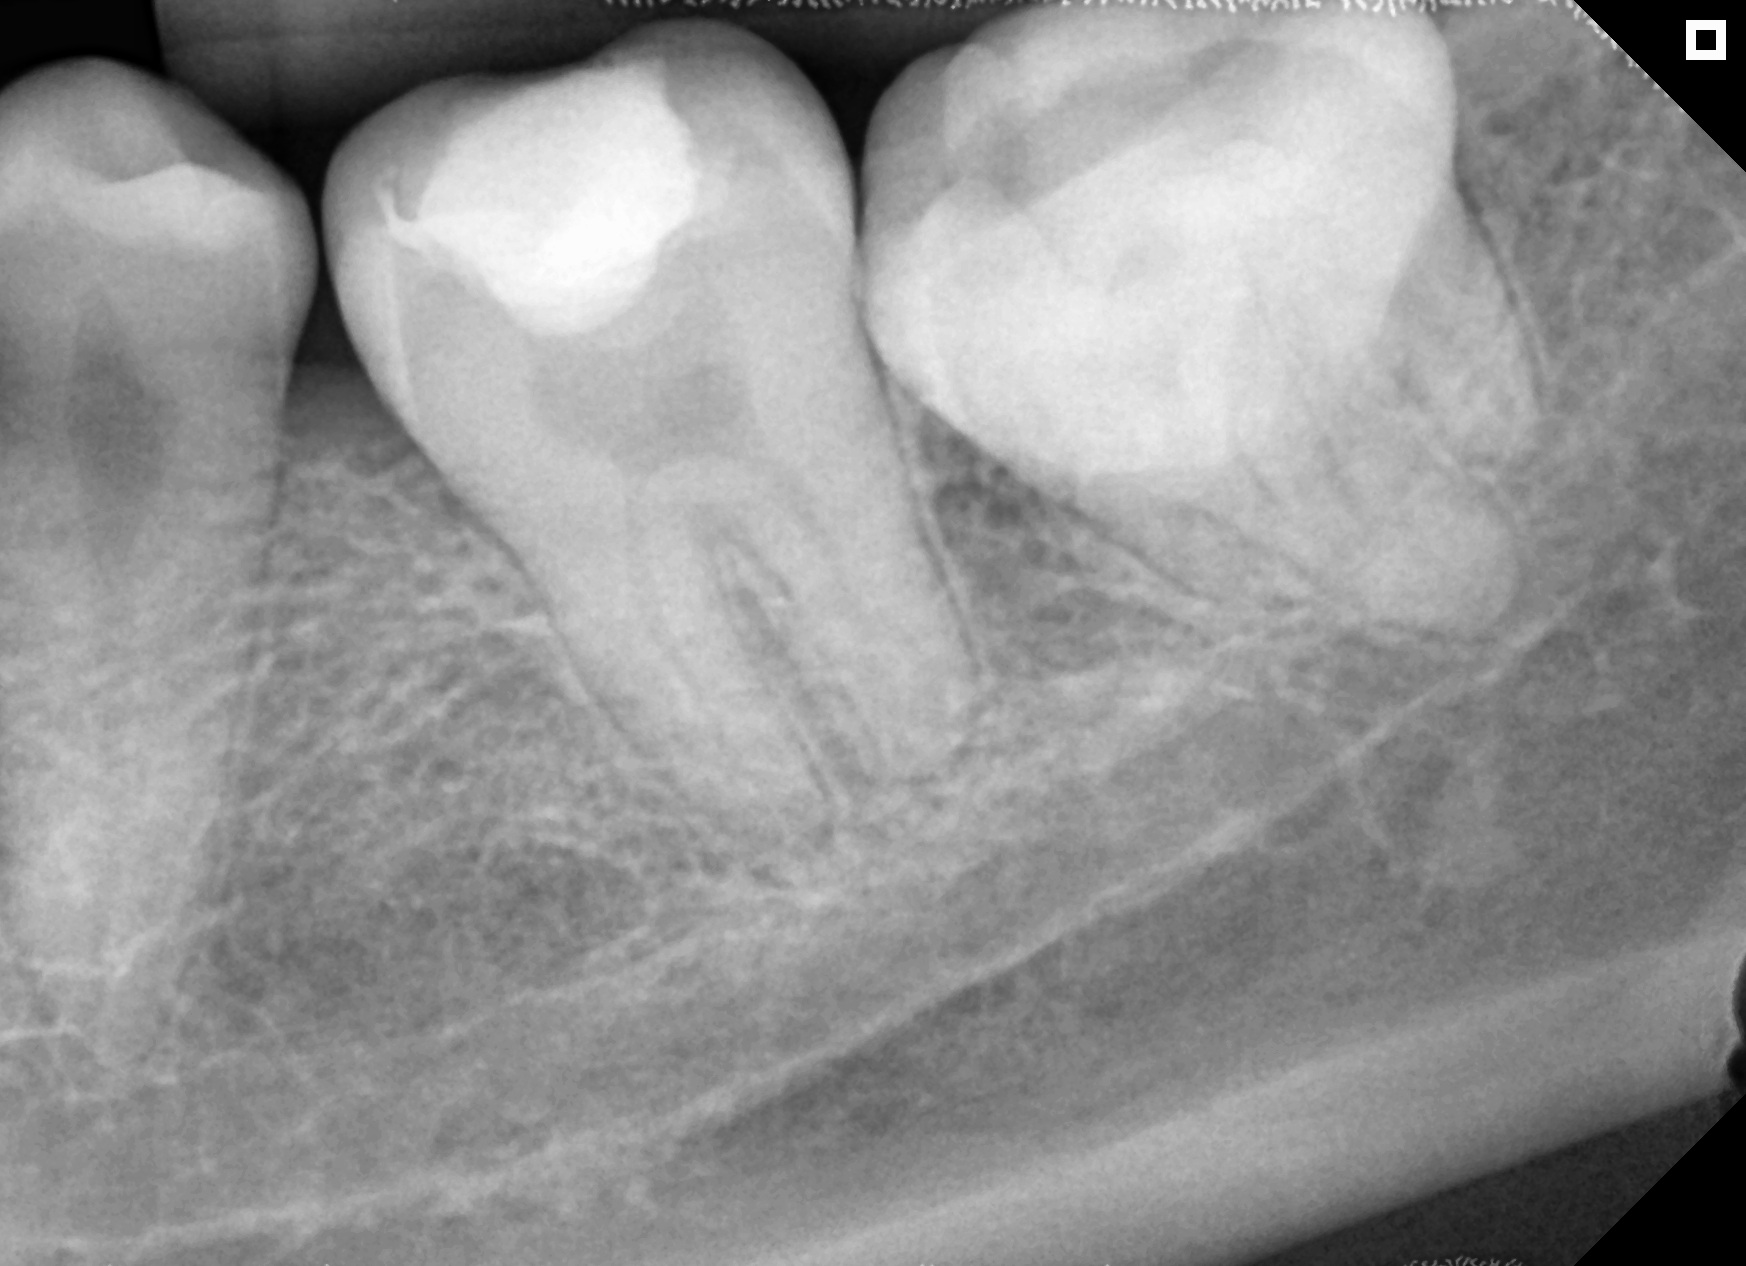

Microscópio e Raio-X Portátil. Equipamentos de última geração e técnicas avançadas para resultados excepcionais e seguros.

Resultados reais com tratamentos personalizados.

Antes

Depois